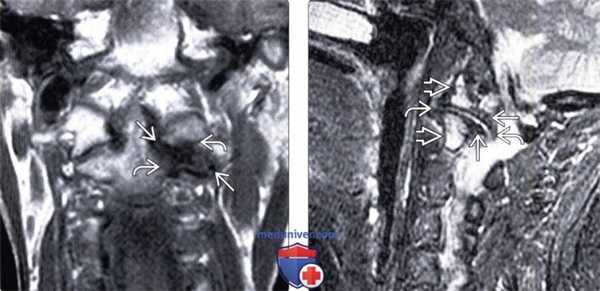

(Слева) На сагиттальной реформатированной КТ в костном окне определяется уменьшение атланто-дентального расстояния в сочетании с остеофитами на вершине. Отсутствие минерализации и наличие остеофитов позволяет исключить болезнь накопления пирофосфата кальция.

(Справа) На сагиттальной МРТ (Т1 ВИ) по средней линии визуализируется большая костная структура над телом С1, предаавляющая собой крупный остеофит у края осевого сустава. Распространенный сигнал низкой интенсивности в зубовидном отростке - нетипичная находка.

(Слева) КТ, сагиттальный срез: сужение атлантодентального интервала, сопровождающееся формированием остеофита на вершине зубовидного отростка. Отсутствие минерализации мягких тканей и наличие остеофитов позволяет исключить в качестве причины наблюдаемых изменений ПА.

(Справа) Т1-ВИ, сагиттальная проекция: достаточно крупное костное образование, расположенное выше тела С1. Это образование представляет собой крупный остеофит, расположенный у края срединного атлантоаксиального сочленения. Распространенное снижение интенсивности сигнала костного мозга в области зубовидного отростка представляет собой зону отека.